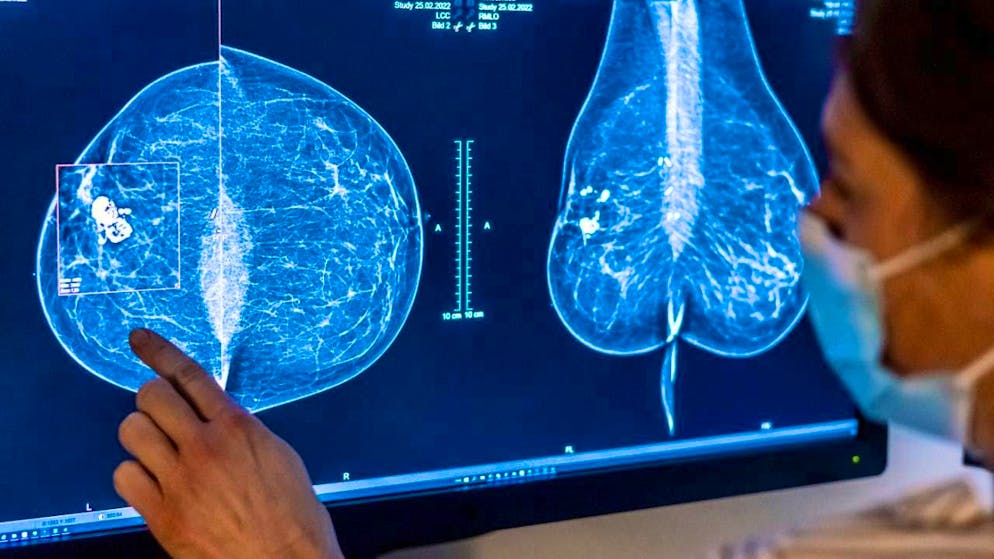

Many cancer cases are due to preventable causes. (archive image)